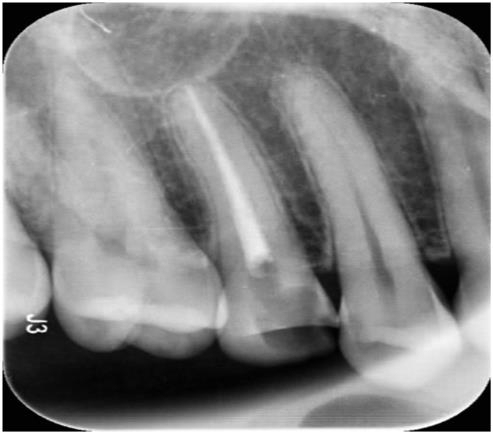

신경치료

Before

After

치아가 많이 썪은 경우 신경치료를 하고 치아를 살릴 수 있습니다.